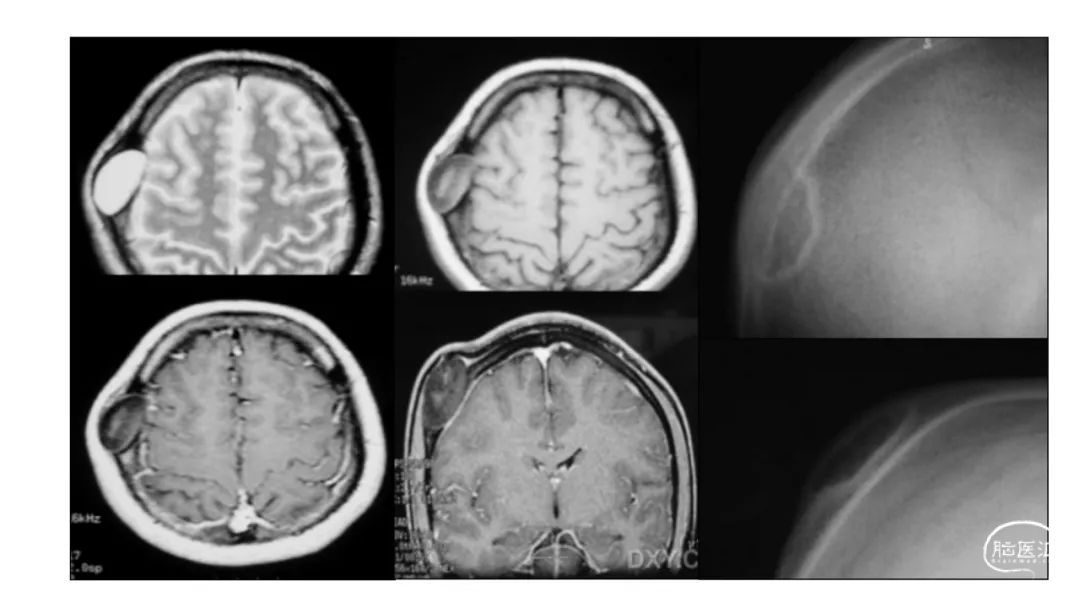

颅脑影像诊断基础知识讲座:颅骨病变